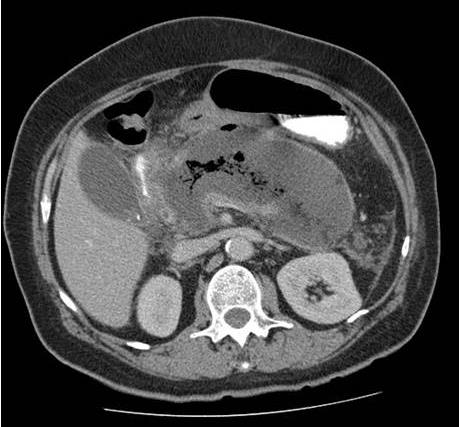

Homem, 48 anos, no nono dia de internação em UTI por quadro de pancreatite aguda necrotizante. No segundo dia, após controle de dor, passou a receber dieta por sonda nasoenteral de forma progressiva e com boa aceitação até o sétimo dia, quando teve recorrência de dor e vômitos, além de três episódios febris em 24 horas e taquicardia sustentada. Atualmente recebendo dieta 1 kcal/mL com volume diário de 1000 mL há dois dias e cinco episódios de vômitos nas últimas 12 horas. Paciente encaminhado hoje para realização de tomografia de abdome com o achado da Figura 11.

Enunciado 3340357-1

Figura 11. Tomografia computadorizada sem contraste de abdome

Tendo em vista a clínica e imagem apresentadas, assinale a alternativa que apresenta qual a hipótese diagnóstica e conduta mais adequada.